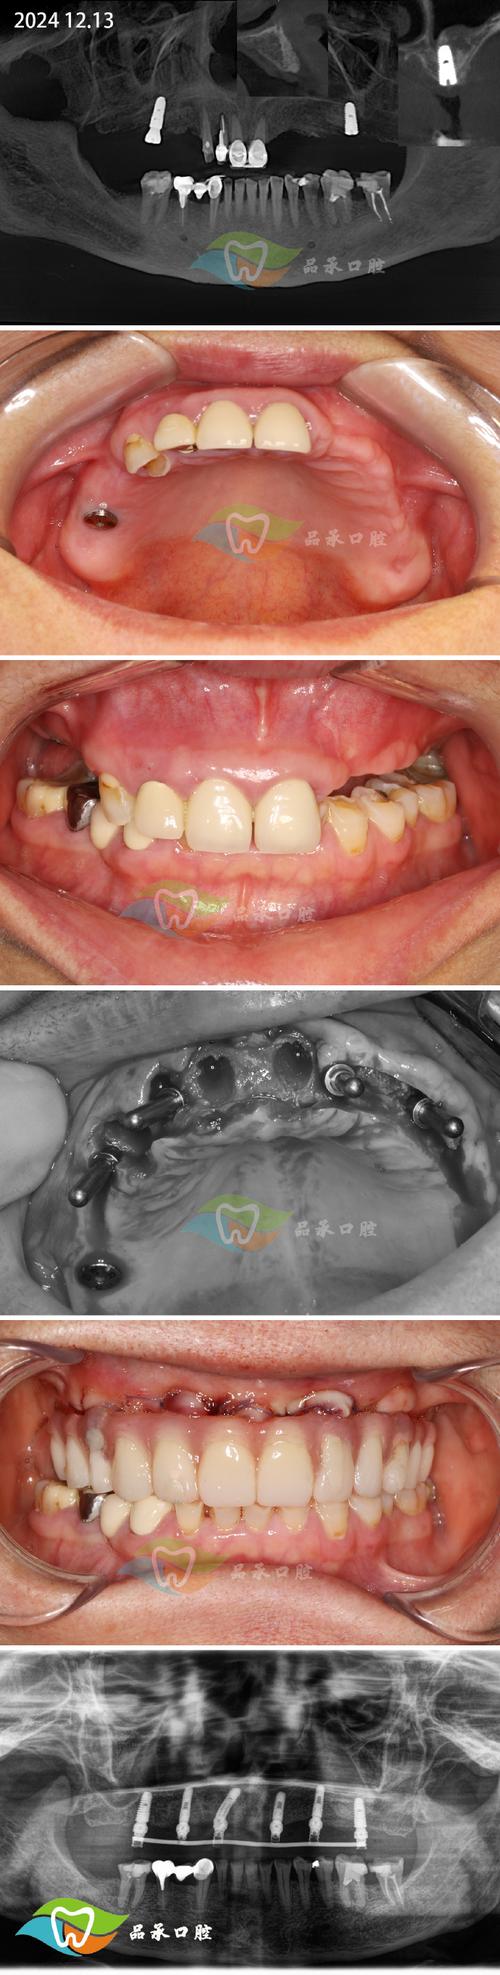

- 骨愈合期: 骨粉(骨移植材料)需要时间与自身骨组织融合(骨结合),这个过程通常需要4-6个月,有时甚至更长,在此期间,绝对不能在手术区域进行任何操作,包括种植牙手术,医生会安排定期复查(拍CBCT或全景片)评估骨愈合情况。